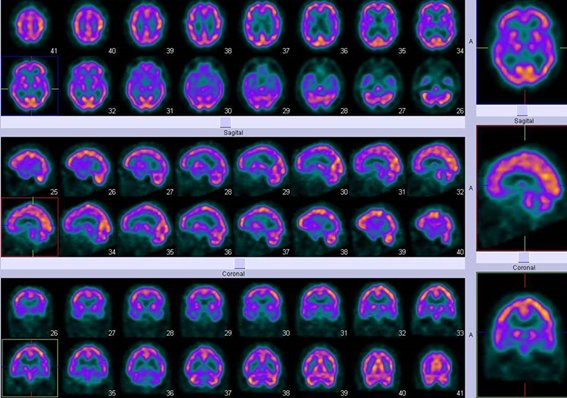

El estudio se realizó mediante inyección endovenosa de 25 mCi (925 MBq) de 99mTc-etil-cisteinato-dímero (ECD), adquiriéndose imágenes tomográficas (SPECT) a los 30 minutos post-administración del trazador. Las imágenes mostraron hipoperfusión temporal izquierda, hallazgo característico de la APP, sin otros cambios significativos en la corteza cerebral, núcleos de la base o cerebelo (figs. 1 y 2).

El hallazgo característico del SPECT y PET en pacientes con APP es la hipoperfusión/hipometabolismo asimétrico predominando en el lóbulo temporal izquierdo(5,6), en contraste con los defectos parietotemporales bilaterales y simétricos de la EA(7). Westbury et al(8) en una revisión de 112 pacientes con APP, de los cuales 59 fueron estudiados con SPECT y PET, encontraron en 97% de ellos anomalías en el flujo sanguíneo cerebral; 69% de los 58 estudios reportados como anormales mostraron alteraciones en el hemisferio izquierdo, mientras que el resto tuvo hipoperfusión bilateral. Sin embargo, se relatan casos de hipoperfusión en el hemisferio no dominante, aunque en forma menos frecuente(9). En nuestro caso, se demostró claramente mediante SPECT una zona hipoperfundida limitada al lóbulo temporal izquierdo sin detectarse cambios sugestivos de encefalopatía vascular o degenerativa de otro tipo, reforzando así el diagnóstico clínico de APP.